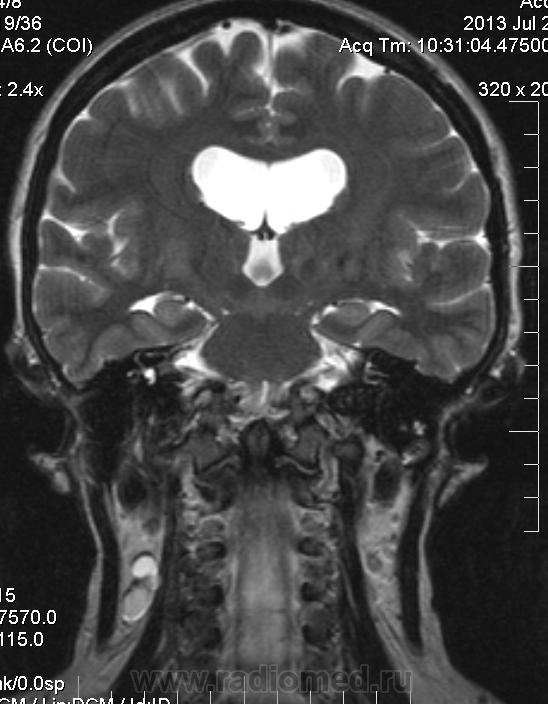

Сирингомиелия шейно-грудной локализации? Аномалия Арнольда-Киари I. Платибазия.

здоровенная сирингогидромиелитическая киста (по видимому, "высокого давления"), мальформация Киари 1.   также имеются признаки внутренней окклюзионной гидроцефалии.

А уровень окклюзии на уровне БЗО?

Думаю, да. У человека наверняка сильно болит голова.